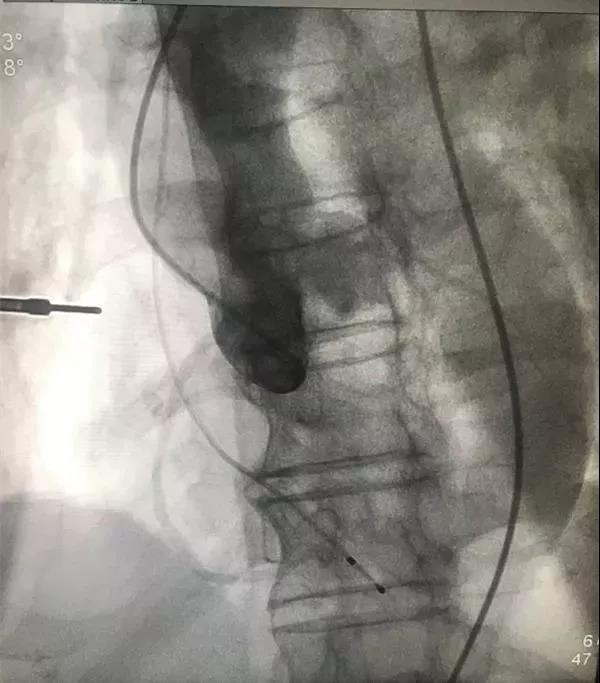

▲主动脉瓣上造影